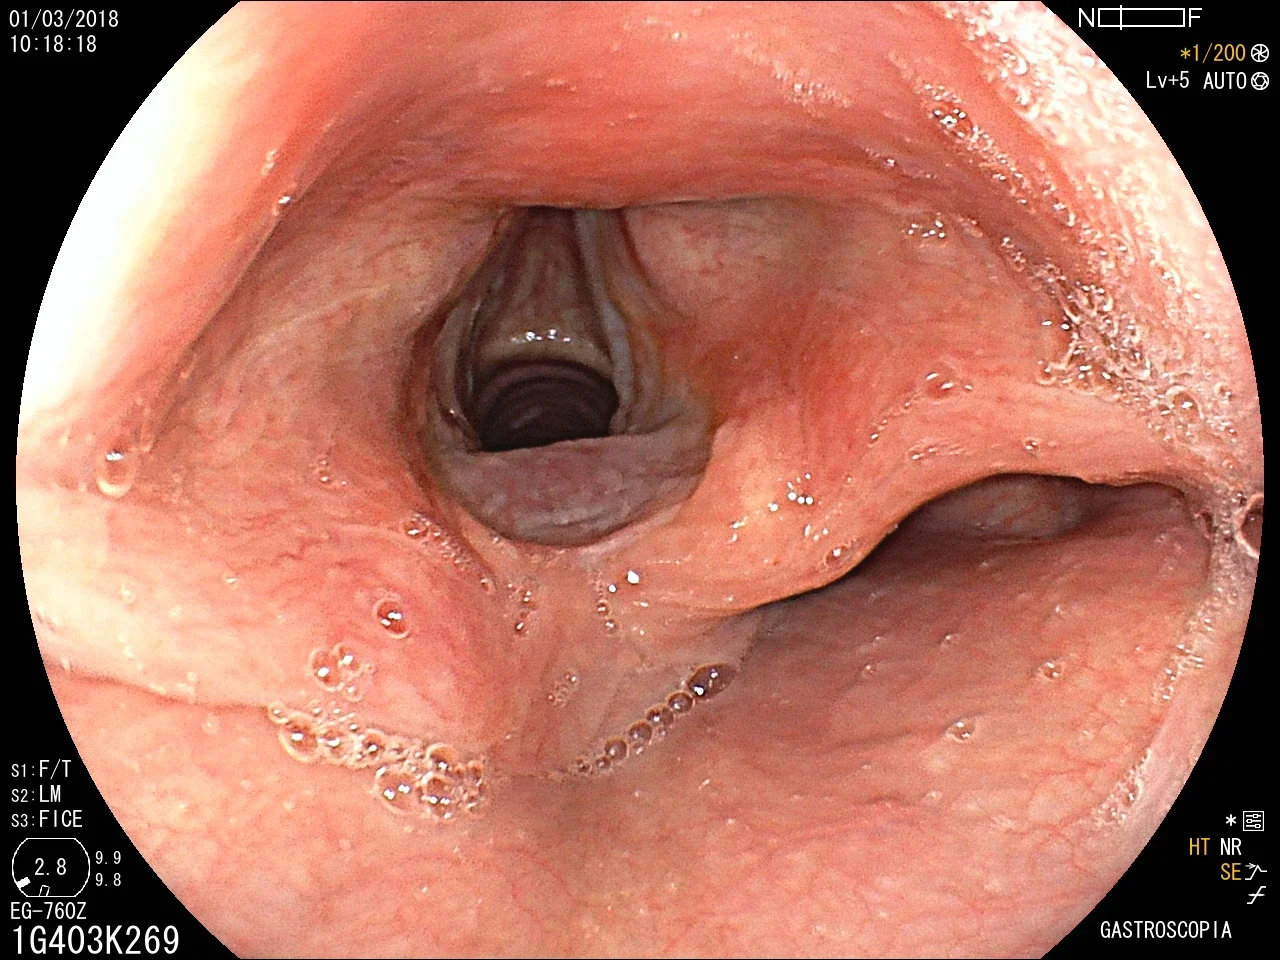

Introducción del gastroscopio bajo visión directa para examinar esófago, estómago y duodeno.

Toma de biopsias de mucosa gástrica o de lesiones encontradas.